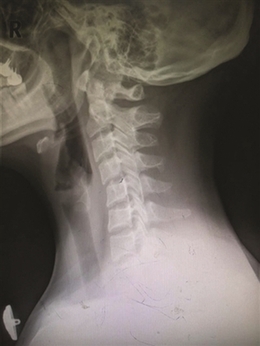

泰勒头颈和身体明显呈一定角度

X光片下已变形的颈椎

非洲原始部落女性,像这样头顶水壶,脖子伸得很直。 上周,第58届格莱美颁奖典礼落幕,美国女歌手泰勒·斯威夫特,这位身高一米八的金发美女一举拿下“年度专辑”等3项大奖。就在前几天,有微信公众号推送一篇文章,指出泰勒有致命缺点——脖子向前伸。 文章说,泰勒的脖子总是往前倾,头颈部和身体呈一定角度。 不过,有研究人员发现,现代人群中,有点脖子向前倾的人还不少。 有研究人类原始姿势的学者Esther Gokhale认为,从远古时期的雕像来看,老底子的人类站立时,脖子都是直的。 Gokhale去了非洲原始部落,观察那里人群的姿态。那里的女性,头顶水壶,脖子伸得很直,全身也是笔直的。她认为,正是因为这些女人颈部姿势正确,才能头顶水壶之类的重物而不会伤到颈椎。 为什么现代人看起来脖子向前倾?Gokhale分析,这与人们久坐不动的时间增加,经常低头看东西有关,“人们缺乏抬头、撑起脖子看远处的活动,所以脖子不自觉地向前伸了。” 这位专家的解释有无道理,我们自己的脖子情况怎么样? 脖子向前伸,是不是一定有颈椎病? 我们在办公室随机做了个小调查,看有多少人的脖子是向前伸的。 25位同事中,基本是三十岁以下的年轻人,昨天下午两点,23位同事坐在电脑前办公。一个个看过来,发现只有三位女同事的脖子没有前伸。 脖子向前伸,是不是一种病? 浙江大学医学院附属第一医院骨科主任林向进主任医师说,脖子向前伸,要分两种情况,一种是生理性的,一种是病理性。 生理性的,人的脖子本来就有韧性,向前向后都可以,经常保持一种姿势,人体习惯了这个体位,脖子就呈向前伸的状态。如果注意一下,人体立即可以恢复正常姿势。 病理性的,就是有颈椎病了,颈椎正常的生理曲度有了改变。正常的颈椎曲度是向前凸的,像一个“(”(见下图),而病理性的曲度变直,甚至反向成为“)”。姿态不太好看,像“乌龟向前伸头”。 “判断颈椎有没有变直或者反弓,不是用肉眼看看就行的,需要拍一张X光片,看清楚每根颈椎和椎间盘的排列。”林向进主任说。

正常的颈椎生理弧线 正常的颈椎有一个凸向前方的生理曲度,生理曲度消失的最初原因是颈部肌肉疲劳,累积到一定程度,颈椎椎间盘病变,椎间盘膨出,压迫神经,就会出现疼痛、胸闷和头晕的颈椎病症状了。 门诊中颈椎病年轻患者增多 他们的脖子也是向前伸 林向进主任医师说,门诊中的颈椎病患者有不少是脖子向前伸的,固定一个姿势,让他们脖子竖起来,都会喊疼。 省中山医院推拿科专门看颈椎病和腰椎病,科室主任吕立江教授说,门诊中超过一半的患者是来看颈椎病的,相对来说,颈椎比腰椎更容易受伤,颈椎附近的肌肉比腰椎要少,更容易受到不良姿势的影响。 本来颈椎病是种“退行性病变”,年纪大了,身体器官用得久老化了,发生了病变。“可现在年轻人得颈椎病的越来越多,主要是他们不注重颈椎健康,保持不良姿势,颈椎提前老化,得了颈椎病。” “最近,有个17岁的学生患者,到我们这里看颈椎,他的样子很特别,头向左前方伸出,好像跳街舞时被定格了。”吕主任说。 寒假就要结束了,他和爸妈约定,最后放松一下:连续三天,他都在夜以继日玩游戏——白天电脑游戏,晚上躲在被窝里玩手机游戏、看视频。前天,骑电动车上同学家玩,被冷风一吹,在一个街口转弯时,脖子被“卡牢”了。 吕主任说,这位学生的颈椎病其实还算轻的。“一直保持一个姿势玩电脑、手机,颈部肌肉劳损了,冷风一吹,肌肉僵硬,这还不是颈椎的问题。如果一直按现在的频率折腾颈椎,颈椎间盘突出等严重的颈椎病,迟早会找上门。” 林主任看门诊有这个感觉,“年轻的颈椎病患者越来越多,他们大多也是喜欢玩电脑、手机。” 浙江大学医学院附属第二医院骨科陈其昕教授说,门诊中经常有会计、文案、IT行业的患者,颈椎病算是他们的职业病。“现在智能手机越来越普及,又有一些新工种加入,比如手机App开发师、手机游戏开发师、微信编辑等。” 颈椎病患者中,手机族比电脑族的病情更有特点,“看手机,头低得更厉害,还合并腱鞘炎;电脑族则比手机族多了腰痛,颈椎不好,腰椎也不好。” 颈椎变形 能恢复到正常生理曲度吗? 陈其昕教授说,颈椎生理曲度,医学上把通过X光片上颈椎向前的弧形凸起称为“颈椎生理曲度”。颈椎生理曲度的存在,能增加颈椎的弹性,减轻和缓冲重力的震荡,防止对脊髓和大脑的损伤。由于长期坐姿、睡姿不良和椎间盘髓核脱水退变,颈椎的前凸逐渐消失,甚至变直或呈反张弯曲,即向后凸,这是颈椎病通过X光片诊断的重要依据之一。 “早期的颈椎弧度变直,仅仅是一个颈椎肌肉疲劳的信号,如果不当回事,颈椎仍旧超负荷工作,积累到一定程度,就会发生颈椎病。” 如果患者出现心慌、胸闷、头晕等交感神经症状,症状越来越顽固,这时颈椎弧度改变就不是单纯的肌肉疲劳信号,而是神经交感型颈椎病的表现;如果颈椎弧度变直并有肢体麻木、胳膊疼痛、走路踩棉花感等脊髓压迫的表现,应该到医院做个颈椎核磁共振检查,是否合并有脊髓型或神经根性颈椎病的可能。 “大家照镜子、拍X光片,发现颈椎生理曲度改变,不要惊慌,不要以为脖子变直了就一定是颈椎病,如果是早期的肌肉疲劳,稍微改变一下坐姿习惯,颈椎的生理弧度会慢慢恢复正常,不会恶化成颈椎病。”陈教授说。 怎么保护颈椎? 试试专家的“仙鹤点水”操 远离颈椎病,应注意两点:一是改变不良姿势,二是,坚持多活动。 怎么活动?大家熟悉的“米字操”,在专家看来,要因人而异。“有些椎间盘型的颈椎病患者,不能做旋转型的运动,不能动得太快,否则,做了反而会加重病情。”林向进主任说。 省中山医院的吕立江教授有套颈椎保健操,几个动作,锻炼颈椎。吕教授经常在门诊里教患者做,大家反响不错。